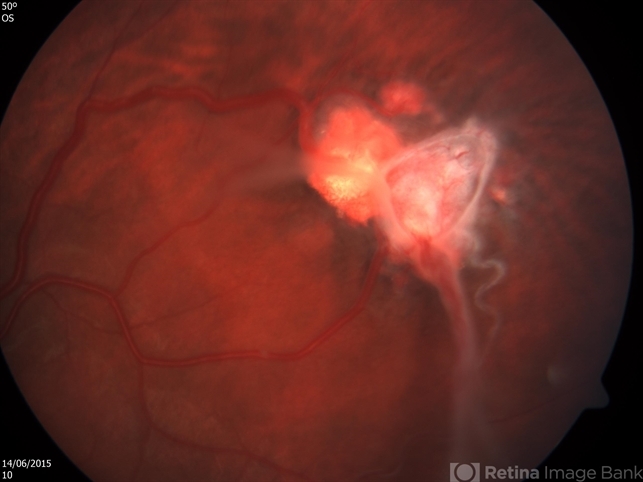

- Retinal Angiomatosis in a 21 Year Old Male

- retinal angioma

- Fundus photograph of a 21-year-old man, who on routine examination was found to have two capillary hemangioblastomas in his left eye. He was diagnosed with retinal angiomatosis.